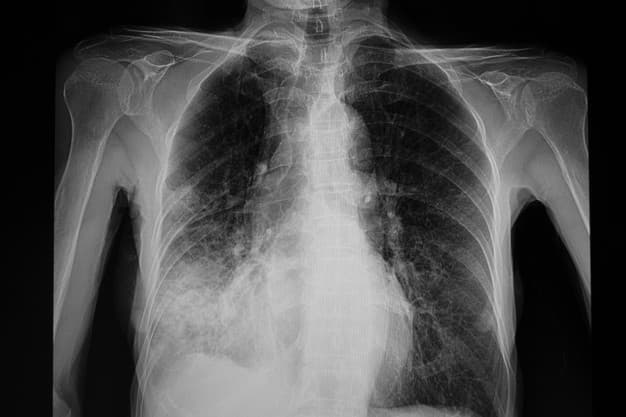

Визначити, чи у пацієнта справді запалення легень, може тільки лікар. Для встановлення діагнозу використовують рентгенологічне обстеження, прослуховування лікарем легень та обов'язково – лабораторні аналізи.

Саме лише рентгенологічне обстеження не може чітко показати, чи у людини справді пневмонія, чи щось інше. Також лікарі можуть використовувати ультра-звукову діагностику легень, але одного цього обстеження для встановлення діагнозу «пневмонія» теж є недостатньо.

«Якщо є зміни на рентгені, то це ще не означає, що у пацієнта пневмонія. Це може бути пневмоніт, викликаний коронавірусом, зміни можуть свідчити про онкологічне чи гематологічне захворювання, тромбоемболію легеневої артерії або інфаркт легень, імунопатологічні захворювання – наприклад, є вовчаковий пневмоніт. Причин для рентгенологічних змін є багато. Тому обов'язково враховуємо інші критерії та аналізи», – пояснює Надія Рудницька.